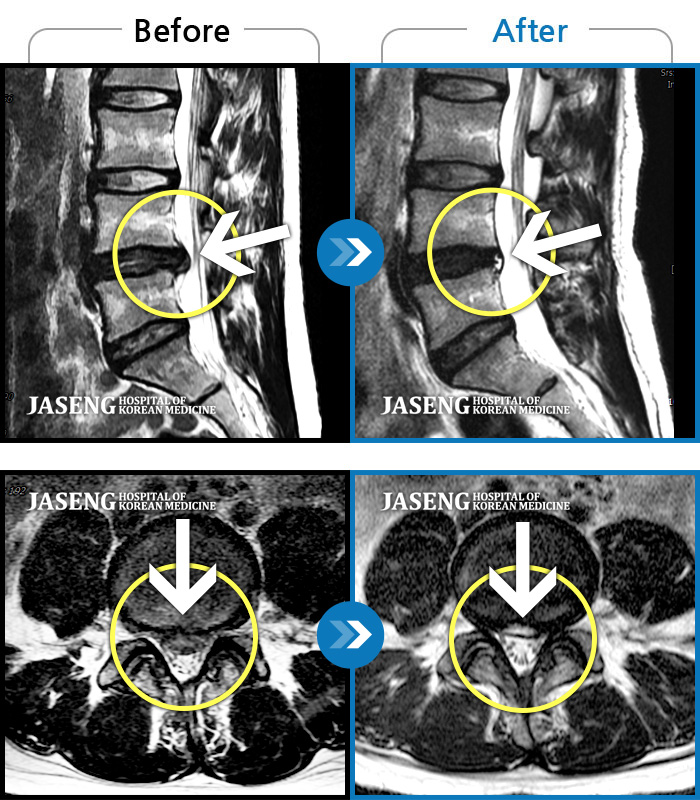

허리디스크

강남 · 강만호 원장

허리 통증 및 왼쪽 다리 근력저하 감각저하로 일상생활이 불가능했습니다.

촬영시기

2024.05.18 ~ 2025.12.03

2025.12.19